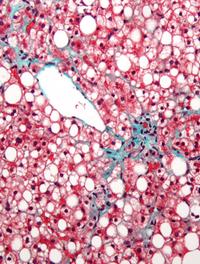

La prise en charge médicamenteuse de la stéatohépatite non alcoolique (NASH) est encore en attente d’une molécule douée de propriétés [...]

Le traitement de la NASH est au cœur d’un enjeu scientifique, médical et industriel sans précédent. Cette affection, corrélée au surpoids [...]

La stéatohépatite non alcoolique (NASH) fait l’objet de nombreuses recherches avec 196 molécules dans le pipeline des traitements en [...]

Le foie gras non alcoolique (FGNA) demeure une affection métabolique dont sa forme la plus grave appelée NASH (stéato-hépatite non [...]

L’hépatite stéatosique non alcoolique est devenue la première des pathologies hépatiques chroniques et l’une des principales causes [...]

La stéato-hépatite non alcoolique (SHNA) est une affection fréquente caractérisée histologiquement par l’association d’une stéatose, [...]